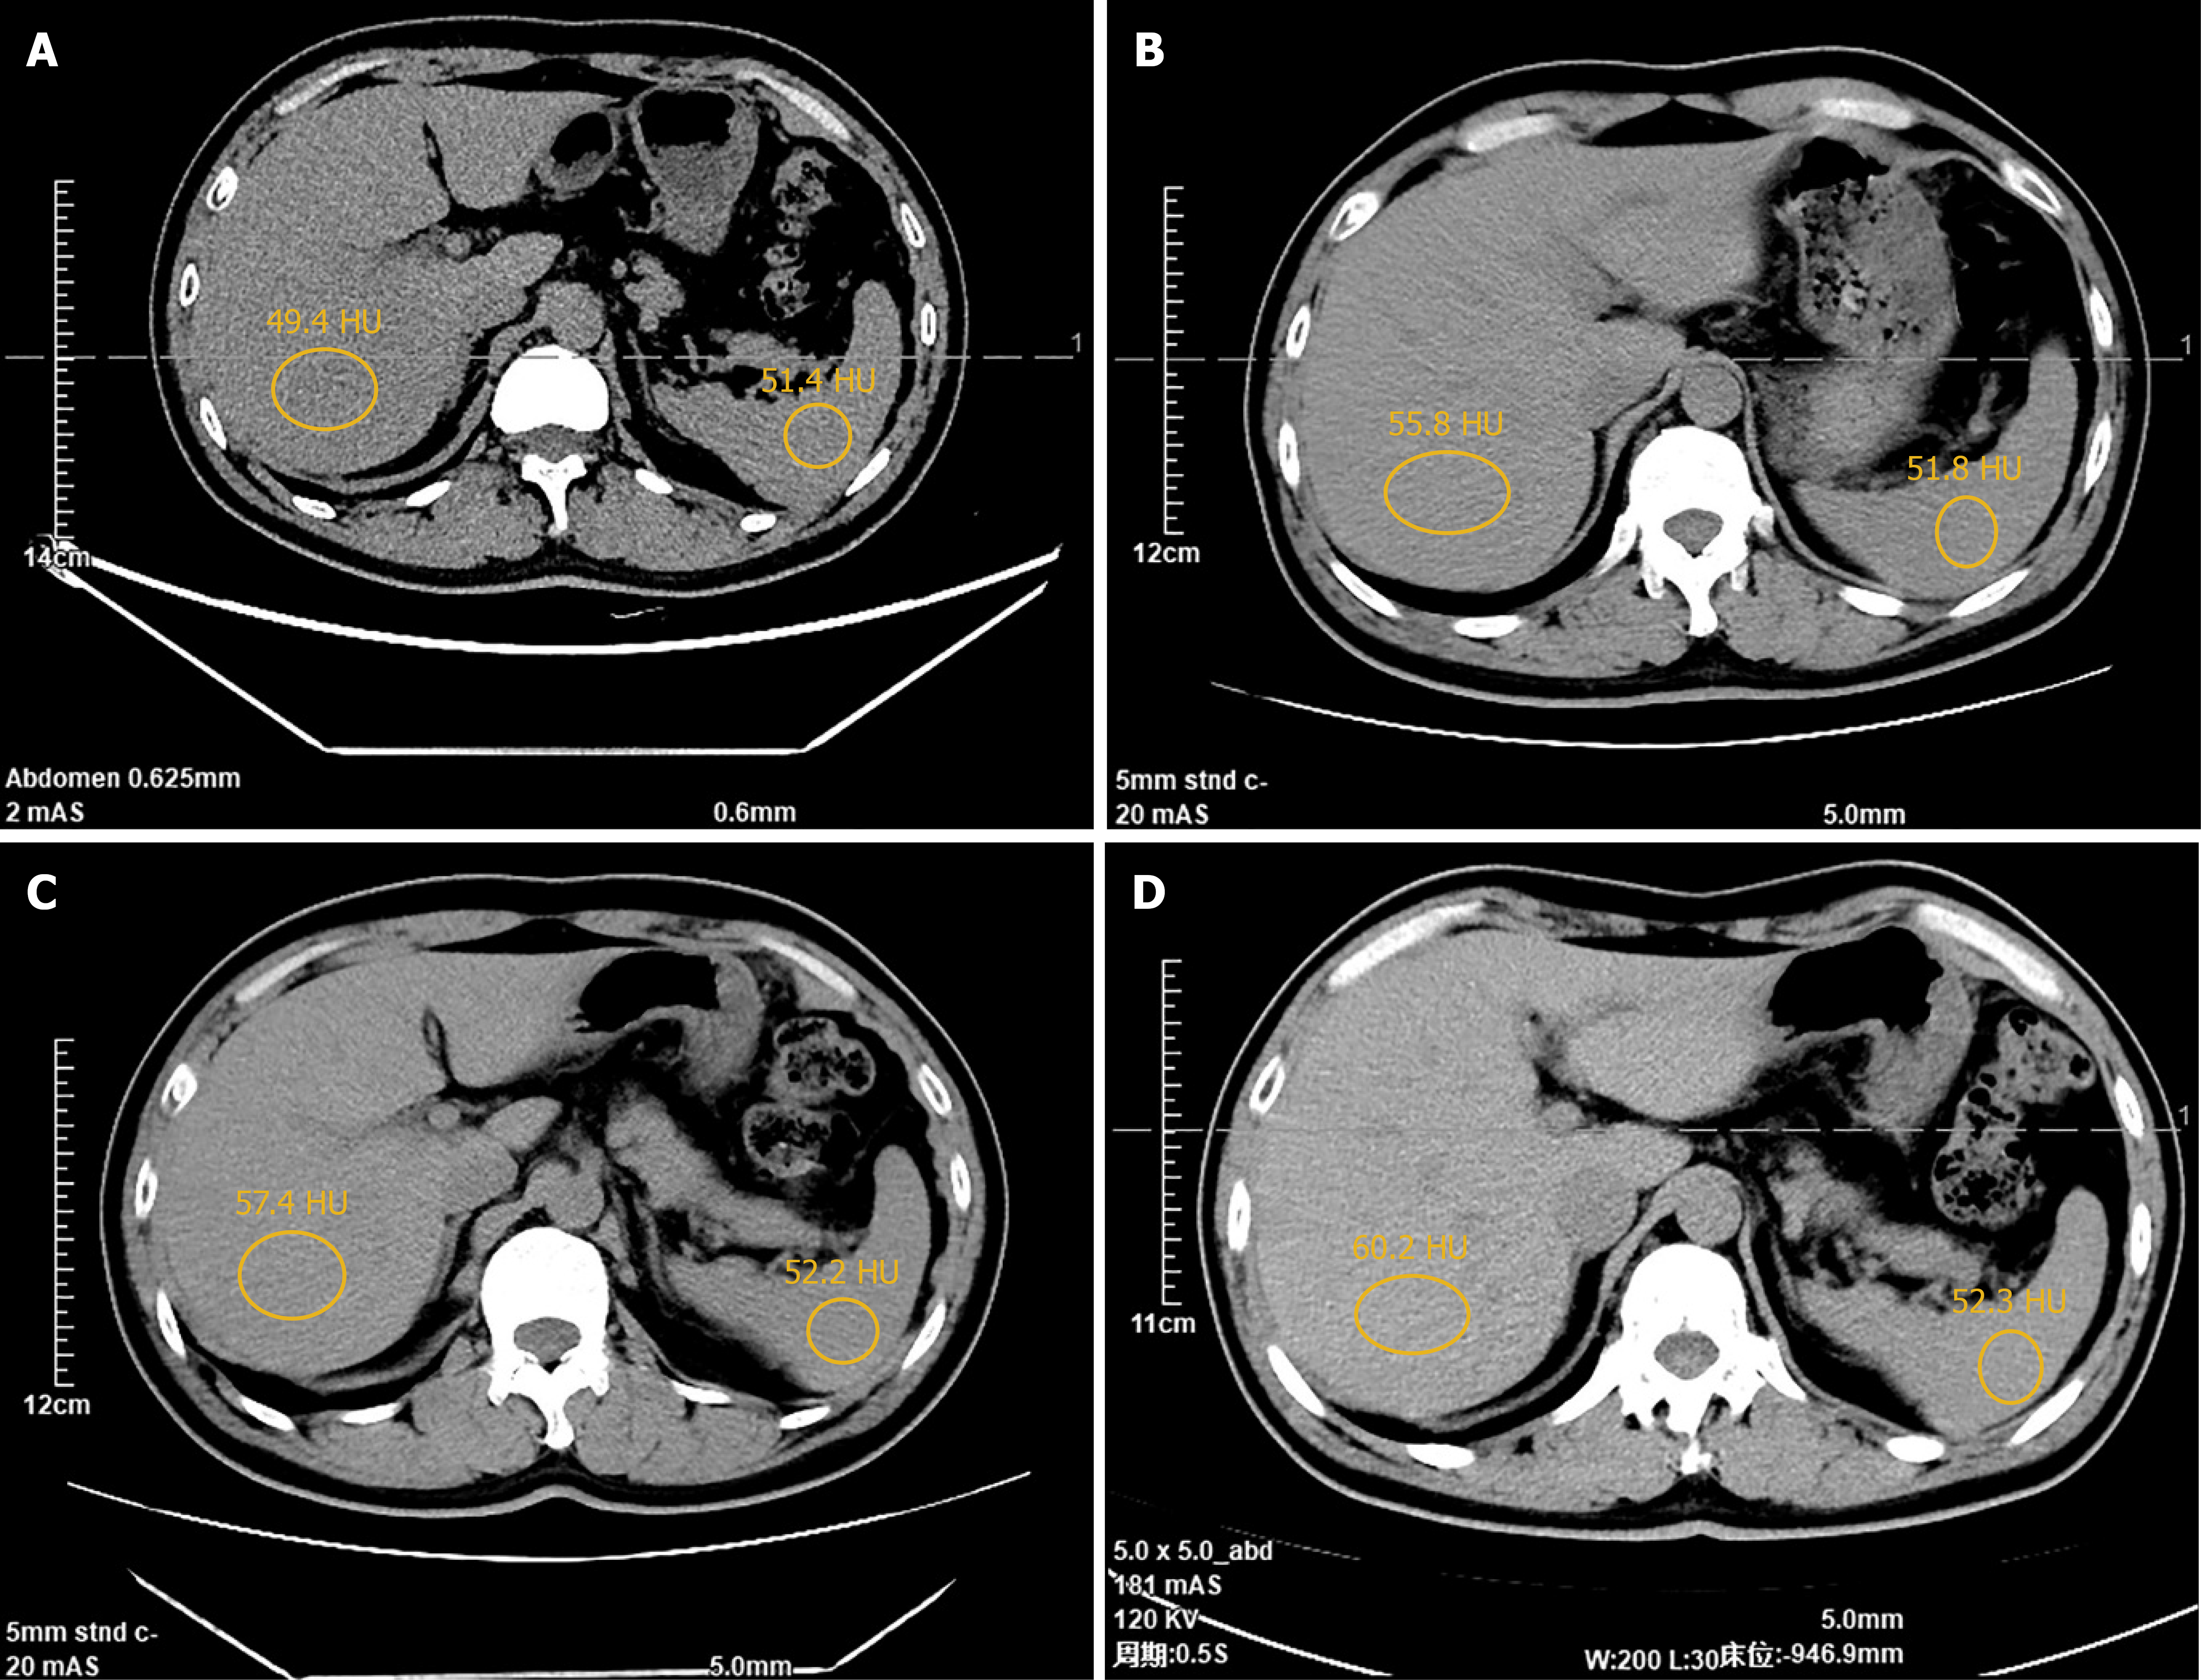

Colonoscopy revealed a 3.5-cm ulcerated, circumferential mass with irregular borders, located approximately 7 cm from the anal verge, consistent with features of malignancy. Histopathological analysis of biopsy specimens confirmed a moderately differentiated adenocarcinoma. Preoperative contrast-enhanced CT of the chest and abdomen demonstrated localized thickening of the rectal wall, without evidence of distant metastasis, including the liver and lungs. Pelvic magnetic resonance imaging identified a mid-rectal lesion with a negative circumferential resection margin (CRM) and no pelvic lateral lymphadenopathy (Figure 1). Baseline unenhanced abdominal CT showed no evidence of hepatic steatosis: Mean hepatic attenuation was 63.8 HU and the liver-to-spleen attenuation difference was 10.4 HU; both well within the normal range. Follow-up unenhanced CT at 6 months and 9 months after surgery revealed newly developed diffuse hepatic steatosis, with mean hepatic attenuation dropping to 27.4 HU and 20.6 HU, respectively, while splenic attenuation remained stable at 45.2 HU and 46.1 HU. After ileostomy reversal, serial CT scans at 3, 6, 9, and 18 months revealed progressive resolution of fatty liver, with complete normalization by 3 months and no recurrence thereafter (Figure 2). Postoperative pathology confirmed moderately differentiated adenocarcinoma with no lymph node metastasis (0/12), and the pathological stage was pT3N0M0. Both the CRM and stapler resection margins were negative.

NAFLD is a spectrum of liver disease characterized by excess hepatic fat accumulation in the absence of significant alcohol intake or secondary causes. Its prevalence is increasing worldwide, with strong associations to obesity, insulin resistance, and dyslipidemia[2,3]. The central pathogenic mechanisms of NAFLD involve overnutrition and insulin resistance, which lead to increased de novo lipogenesis, impaired lipid oxidation, and inflammatory responses in hepatocytes[4,16]. While most cases of NAFLD are associated with classical metabolic syndrome, our case illustrates a distinct etiology - transient enterohepatic hormonal dysregulation triggered by loop ileostomy. Several features in this patient support this hypothesis. First, although CT has limited sensitivity (46%-72%) for detecting early or mild steatosis[17], baseline abdominal CT scans showed no signs of hepatic steatosis with liver attenuation measuring > 60 HU and a liver-to-spleen attenuation difference > 10 HU (Figure 1). However, follow-up CT imaging at 6 months and 9 months postoperatively demonstrated new-onset diffuse hepatic steatosis with liver attenuation < 40 HU and a liver-to-spleen attenuation ratio of < 0.8, meeting the diagnostic criteria of hepatic steatosis[17] (Figure 3). The consistent progression and resolution pattern of hepatic steatosis on serial CT imaging, along with corresponding metabolic changes, support the temporal association with ileostomy status. Second, the steatosis reversed completely within 3 months of stoma closure, without lifestyle or pharmacological intervention. Third, the temporal trends in BMI, lipid profiles, and VAS-based appetite scores mirrored the radiologic course of hepatic steatosis. Finally, serial hormone assays revealed significant alterations in GLP-1 and PYY(3-36) concentrations before and after stoma closure, implicating a possible endocrine mechanism.

Figure 3

Figure 3 Postoperative abdominal computed tomography scans obtained at 3, 6, 9, and 18 months after the reversal operation. A-D: Scans correspond to the 3-, 6-, 9-, and 18-month timepoints, respectively (the circle hepatic/splenic attenuation in HU: A: 49.4/51.4; B: 55.8/51.8; C: 57.4/52.2; D: 60.2/52.3).